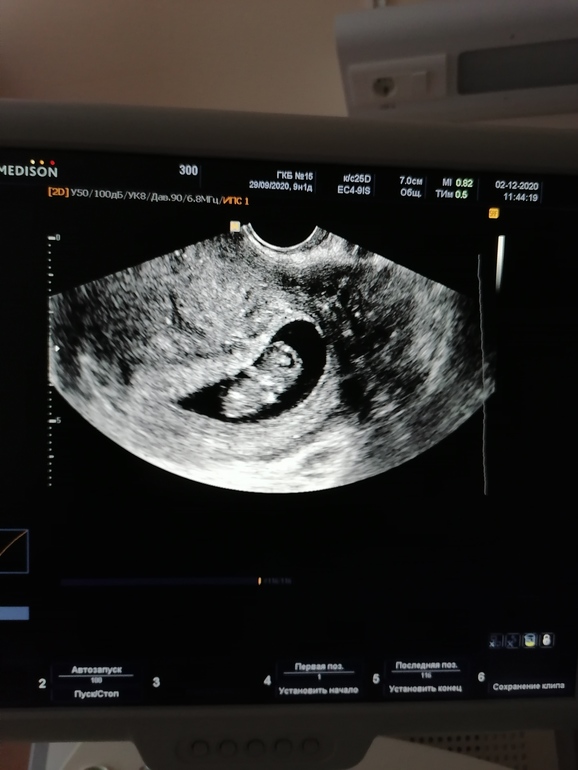

Ну и добавлю своего колобочки 💙💙💙🙏. Такой забавный, как каратист руками, ногами махал🥰. И опять опережает в размерах. По М срок 9.2 а по УЗИ 9.4.

Киста из ПЯ ушла урааа, а в ЛЯ киста ЖТ ещё есть.